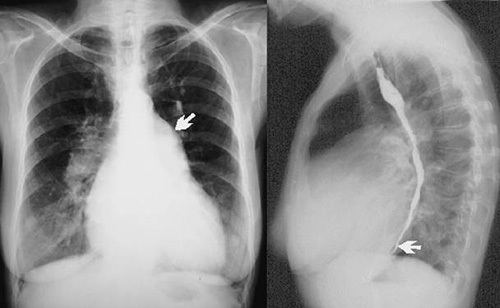

Рис. 213. Ангиограммы легких в прямой и левой боковой проекциях. Контрастирова-ны правый желудочек и разветвления легочной артерии.Магистральный тип ветвления сосудов легких.

7 — правый желудочек; 2 — артериальный конус; 3 — легочный ствол; 4 — правая легочная артерия; 5 — левая легочная артерия; 6 — правая верхняя долевая артерия; 7 — левая верхняя долевая артерия; 8 — правая нижняя долевая артерия (нижний ствол); 9 — левая нижняя долевая артерия

(нижний ствол).

Прямая проекция. Легочный ствол (3) образует вторую дугу сердца по левому контуру. Место деления его на ветви, а также правая легочная артерия и начальный отдел левой при обычном рентгенологическом исследовании не видны, так как перекрываются срединной тенью (рис. 213).

Правая легочная артерия (4) при контрастировании видна на фоне срединной тени в виде широкой полосы 20-28 мм в поперечнике, расположенной горизонтально или несколько наклонно книзу. Соответственно уровню переднего отдела II ребра, еще в средостении, правая легочная артерия делится на две ветви, которые в рентгенологической литературе носят название верхнего и нижнего стволов.

Боковая проекция. Легочный ствол расположен по продолжению артериального конуса правого желудочка и проекционно совпадает с восходящей аортой. При контрастировании дифференцируется книзу и кпереди от раздвоения трахеи.

Правая легочная артерия дает интенсивную округлой или овальной формы тень в корне правого легкого, отчетливо определяемую лишь при контрастировании. При бесконтрастном исследовании контуры ее видны нечетко из-за проецирующихся сегментарных сосудов.

Левая легочная артерия образует дугообразную тень, огибающую округлое просветление поперечного сечения левого главного и верхнего долевого бронхов, нижний ствол ее отклоняется кзади.